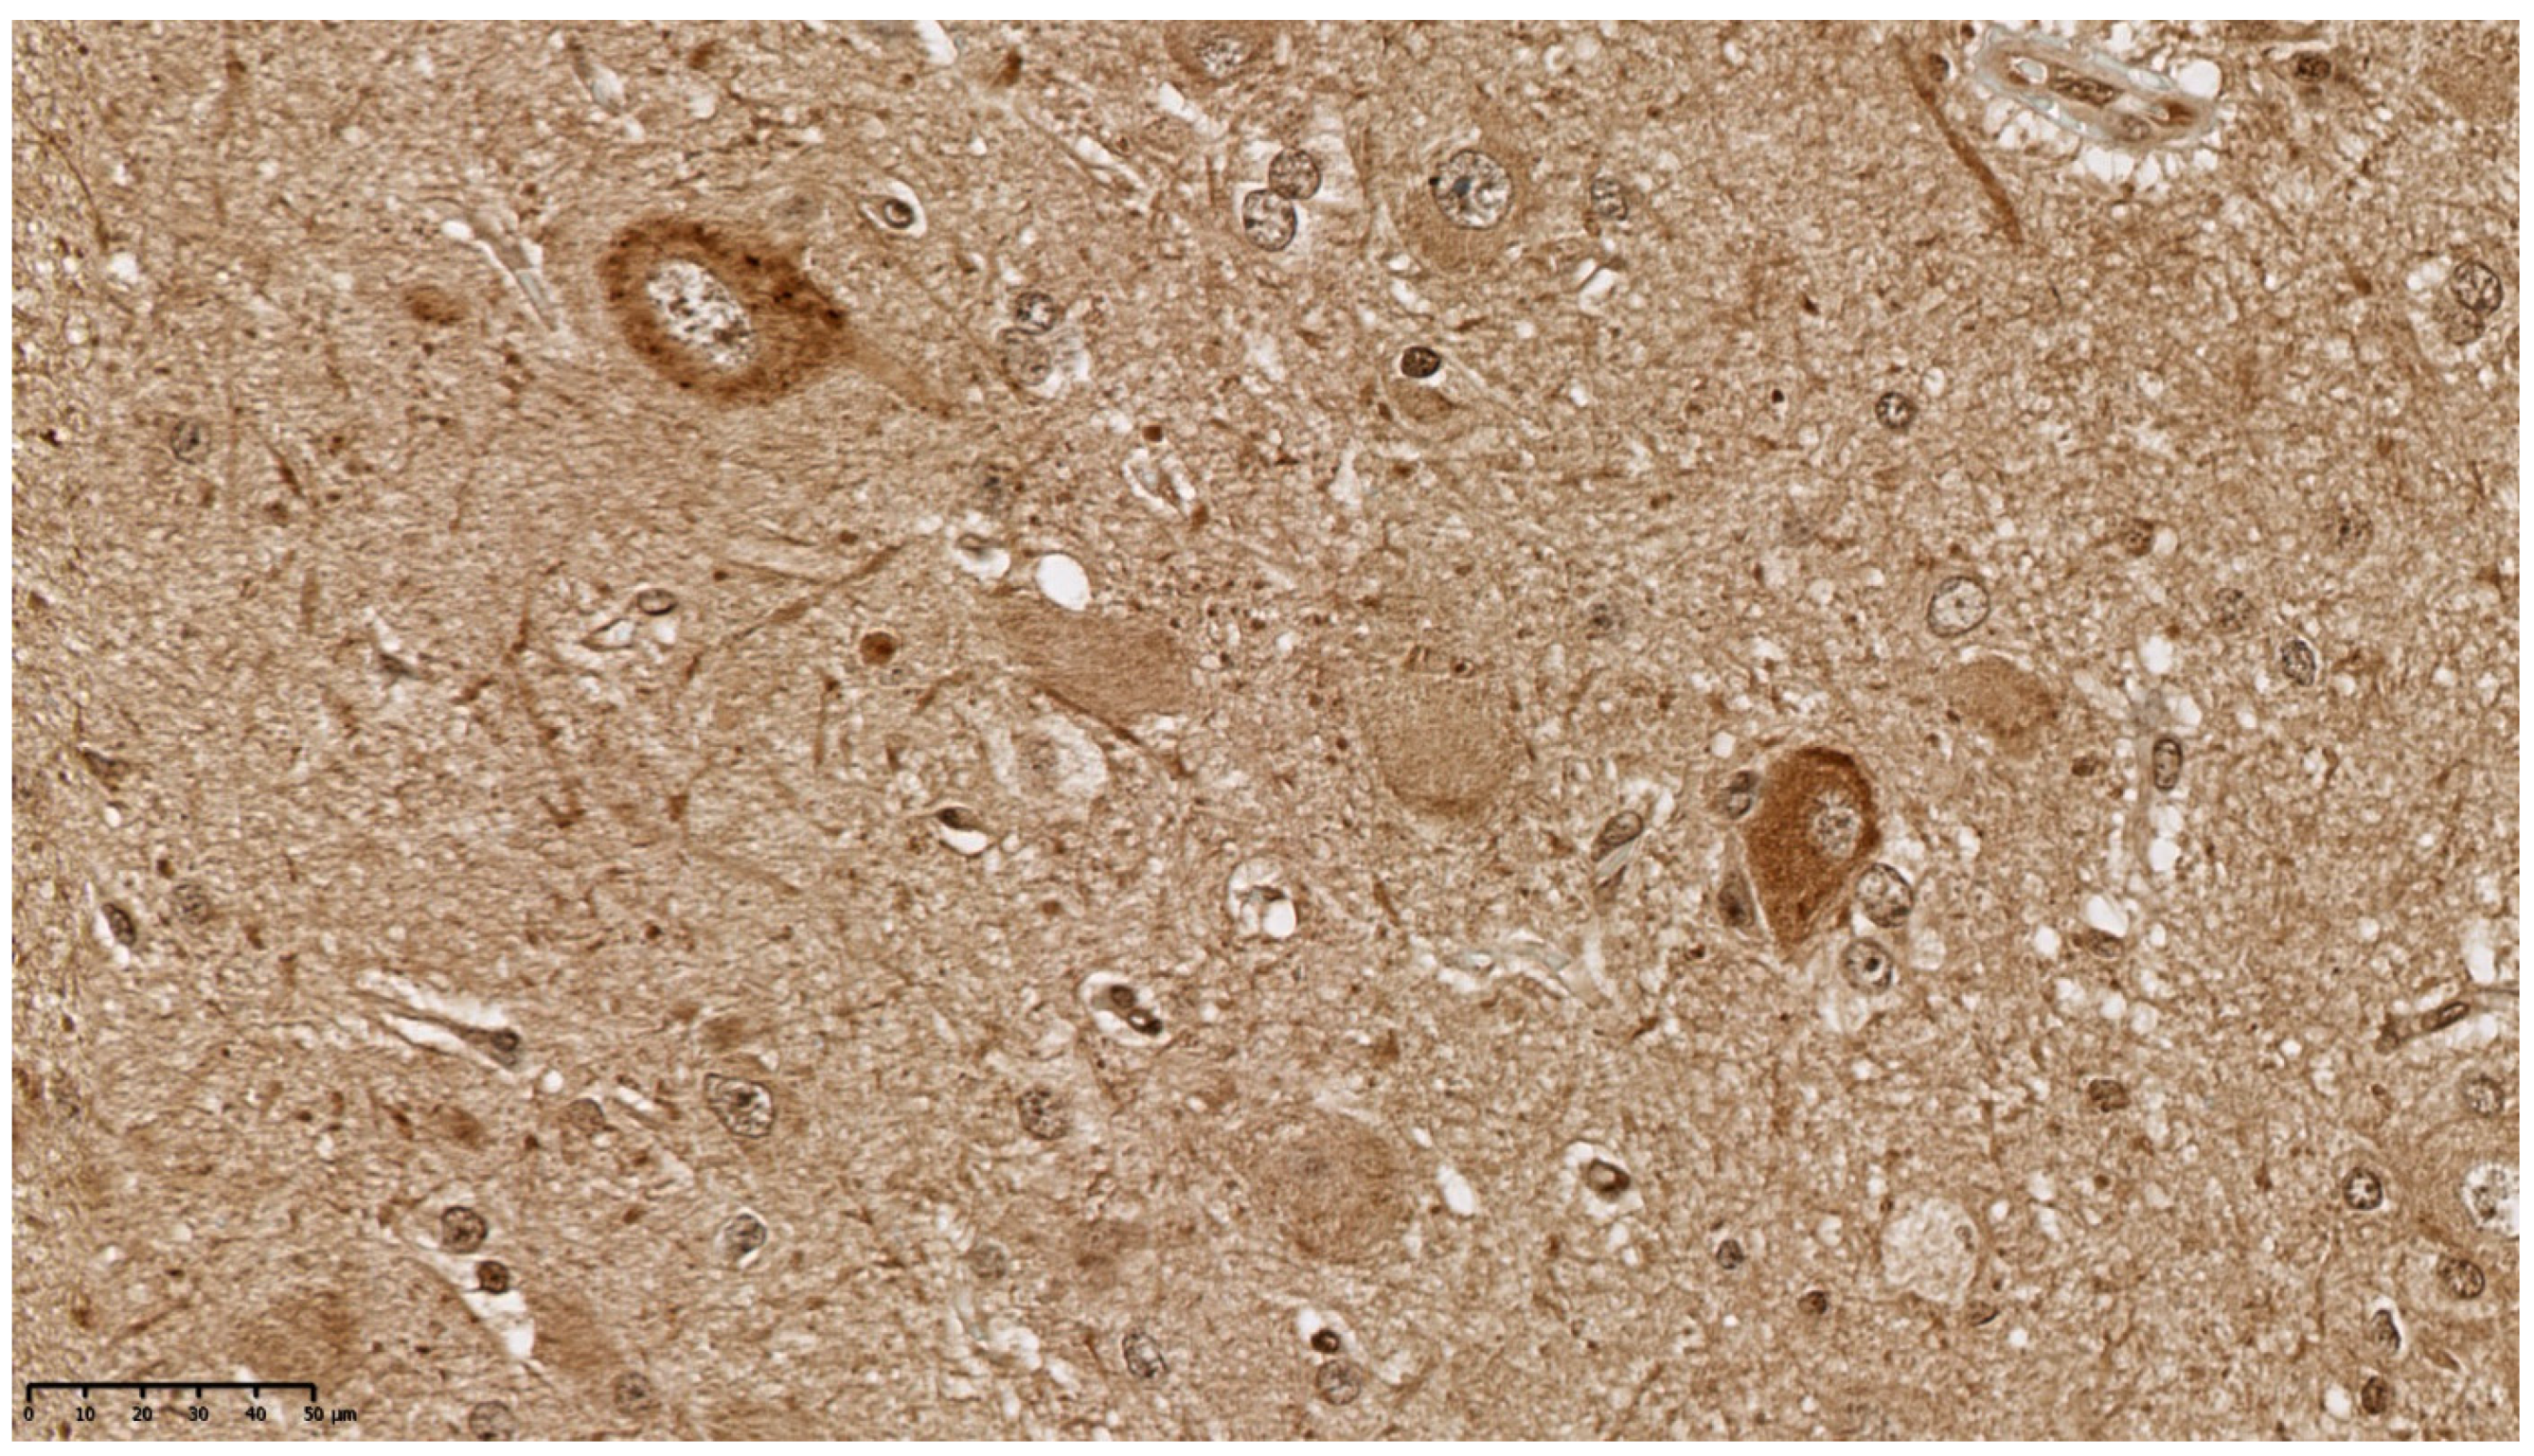

3.1. Clinical and Pathology Report